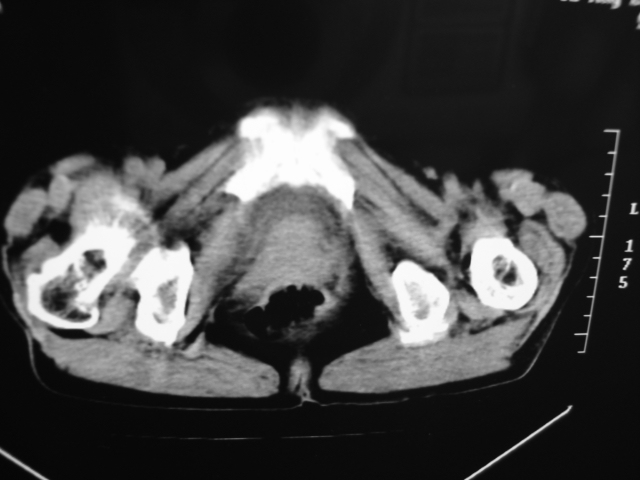

同事奶奶,73岁,腹痛一年,夜晚较重,潜血+++,拒绝增强,考虑左肾ca并腹膜后转移;请各位老师帮忙看看,谢谢!

左肾癌侵及输尿管上段,腹膜后多发淋巴结转移,脾脏钙化灶。至于潜血+++,要考虑消化道病变,本次ct片肠腔未见明显异常。

潜血+++是尿还是便?如果是便,则考虑肾癌侵犯降结肠可能。

1)考虑左肾癌侵犯肾盂并腹膜后淋巴结转移。2)脾脏钙化灶。

查查一胸部,不除外肺癌伴左侧肾上腺,腹膜后淋巴结及左肾转移.

定位像见上肺野也很糟糕,支持7楼。

考虑左肾癌侵犯肾盂并腹膜后淋巴结转移。